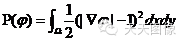

当然,他干的有影响的不止这一件事,不过这是开始。一言以敝之,就是在原始的方程中添加了下面的二阶式子,作为惩罚项。

它的微分如下:

1-1/|▽φ|被称为扩散率函数,当水平集函数梯度大于1时,扩散率大于0,惩罚项起正向扩散作用,使得水平集函数更加光滑,从而减小梯度;反之使其增大。总之,它约束了水平集函数的梯度偏离1的程度,而当水平集函数的梯度能保持1时,对应的零水平集,也就是我们的分割轮廓是光滑处处连续可导的。后来李进一步改善了该算子,使得水平集函数在零水平集附近的梯度为1,而在远离零水平集的附近为0。当然也有人基于此方法的思想,采用了更加高阶的规整化方案。

好了,核心思想是什么?

那就是,如果曲线演化速度太快了,就让它慢一点,如果慢了,就快一点。它的存在,能在很大程度上保证零水平集曲线是光滑的。水平集函数φ不光滑的地方,▽φ就会大于1,从而使得P很大,对减小能量造成不利的影响。所以P是一个惩罚项,要想能量最小,作为它的求和项中一项的P也应该小,对应的也就是曲线光滑,不知道这样理解是不是简单一些?

有了这一项后,就只需要考虑以一定的步长进行离散迭代,而不需要每迭代一次就对水平集函数Φ进行一次复杂的计算了。